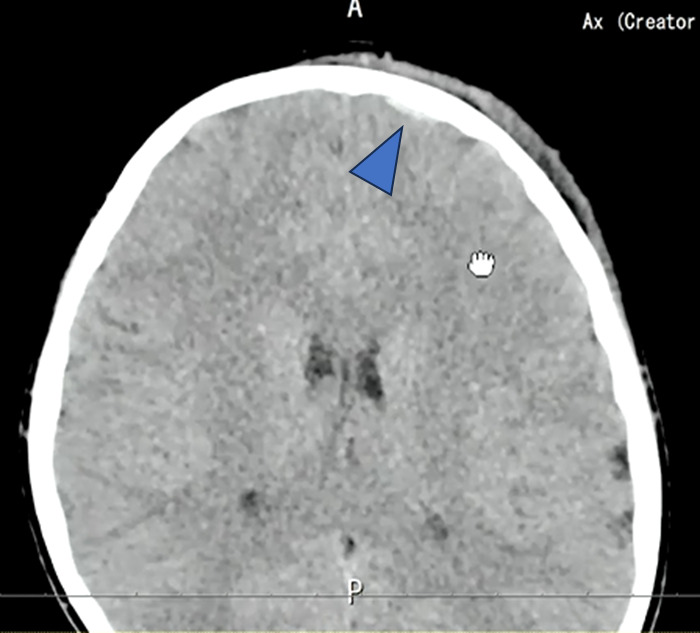

矢印の部位でわずかにここに出血があります。

軟部条件では観察しづらいのですが、WLを50、WWを100程度に設定すると、

わずかに高吸収域を認めます。外傷後の外傷性硬膜下出血と思われます。

もう1つ高吸収域が存在しています。

矢印の部位について、臨床の先生から”脳挫傷”があるのではないかと再読影の依頼が来ました。

受傷日と翌日のCTと比較すると、確かに出血が顕在化し、目立っておりわずかな硬膜下血腫もしくはくも膜下血腫と脳挫傷の可能性があると再読影をしました。

小児は骨が柔らかいため、外板のみが折れて陥没し、完全骨折に至らず所見が目立ちにくいことがあります。出血も初期は少量で、時間経過とともに明瞭化しました。本症例は外傷性陥没骨折、外傷性くも膜下出血・硬膜下血腫、脳挫傷と診断されました。